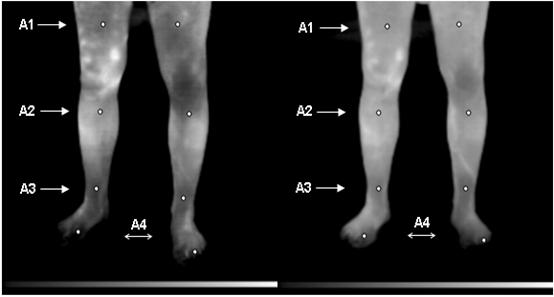

Значения температуры в контрольных точках нижних конечностей до и после внутривенного введения 200 мл перфторана и термограмма представлены в табл. 10 и на рис.21. После введения перфторана максимальные изменения регистрировались на стороне наибольшей выраженности патологического процесса – стопы левой ноги, что свидетельствует о выраженном улучшении кровообращения системе микроциркуляции под влиянием перфторана.

До введения перфторана | После введения перфторана |

Рис.21. Термограмма при облитерирующим эндоартериите IIА стадии.